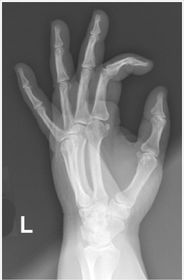

| PA Hand | distal phalynxes are bent flatten hand to true PA *should be equal concavity on all digits* |

| PA Hand | obliqued - fingers are not equally concave on both sides distal metacarpals are overlapped |

| PA Hand | ANATOMY: entire hand including 1'' of distal radius and ulna CRITERIA: equal concavity on either side of digits digits separated with no superimposition open joint spaces POSITIONING: CR perpendicular @ 3rd MCP joint |